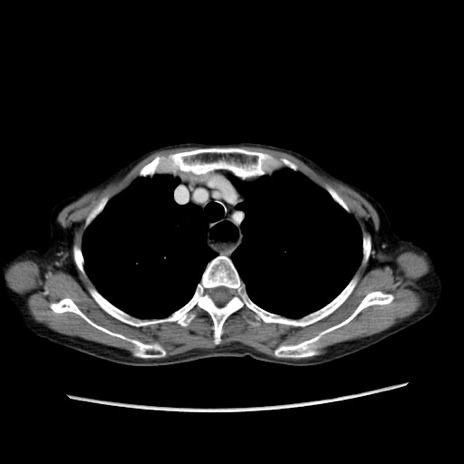

症例25(横断像)

【症例】80歳代女性

【主訴】胸のつかえ感

【現病歴】約9時間前に食後から胸のつかえた感じあり、嘔吐あり、来院。

【既往歴】胃癌(全摘)、胆摘、虫垂炎

【身体所見】心窩部に圧痛あり、反跳痛なし。

【データ】WBC 5700、CRP 0.05